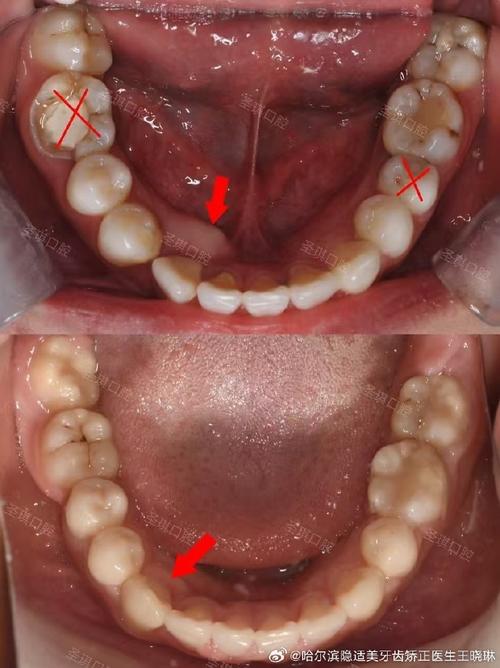

- 替牙期障碍:乳牙早失导致邻牙倾斜占据空间,使恒牙萌出间隙不足;乳牙滞留或多生牙、埋伏牙等,会阻碍正常恒牙排列,引发“虎牙”或牙齿扭转。

- 初诊检查:包括口内检查、模型制取、X光片(曲面断层片、头颅侧位片)及CBCT(三维影像),分析牙齿、颌骨、咬合关系,制定个性化方案。

- 方案设计:根据患者年龄(儿童可能需配合生长改良治疗)、畸形类型、诉求选择矫正方式,必要时需拔牙(解决牙量骨量不调)或辅助支抗钉增强控制力。